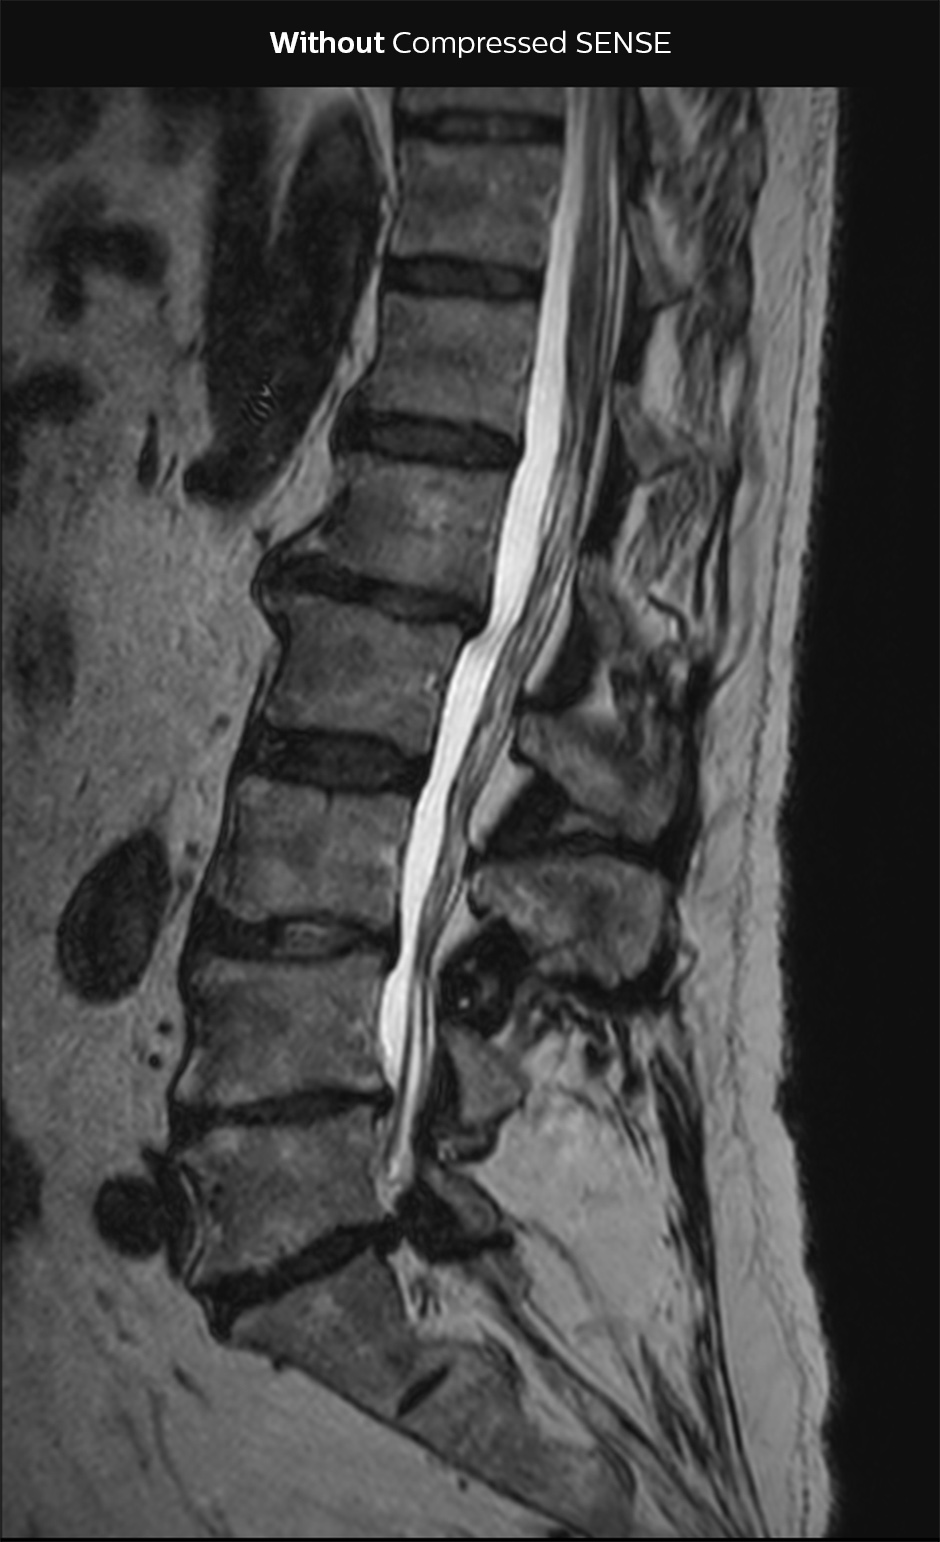

“Our aim for the spine is to use Compressed SENSE to help us make the switch to using 3D SpineVIEW. In lumbar spine, for example, we can reduce scan time for 3D T2W SpineVIEW by 27% to 4:46 minutes, voxel size 0.8 x 0.8 x 1 mm."

“In the end, we would like to just perform a 3D T2W, and 3D T1W, and a STIR T2W for cervical and lumbar spine imaging, and then do secondary reconstructions. That’s why we need high resolution for the 3D sequences, and combining with Compressed SENSE then helps to reduce scan time. In this way, replacing the 2D sequences with 3D sequences is much better for the patient, because we can reduce the time of the scan. Another advantage is that if sometimes a scan is not done properly, we have more freedom to do reconstructions afterwards with the 3D sequences and still make a confident diagnosis from the exam.”

In this example Compressed SENSE has a 26% shorter scan time and improved spatial resolution simultaneously.

3D T2 SpineVIEW, scan time 6:29 min, voxel size 1 x 1 x 1.4 mm

3D T2 SpineVIEW, scan time: 4:46 min, voxel size 0.8 x 0.8 x 1 mm